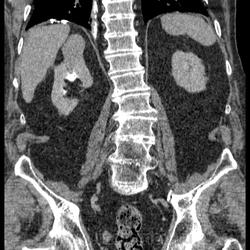

КТ ОБП+С Объемное гиперваскулярное образование почки. Почечно-клеточный рак.

Мужчина 82 года. Отец коллеги с другого отделения. На УЗИ киста почки. Решили сделать КТ. Жалобы на боль в поясничном отделе позвоночника (неудивительно из-за жуткого остеохондроза и м/п грыж). Макрогематурию отрицает. Микрогематурии не выявлено по ОАМ, лишь протеинурия. Кисты подтвердились ну и черт с ними  хуже то, что в верхнем сегменте правой почки похоже ПКР, характеристика контрастирования соответсвует, тем более еще свеж в памяти предыдущий случай. Смущают надпочечники, не "стрельнул" ли в правый mts? А в опухоли гиподенсивный учаток в артериальную фазу - участок некроза, кровоизлияния?

Почечно-клеточный рак, гистологически - светлоклеточный, степень дифференцировки не помню.

Образование в верхнем полюсе правой почки: гиперденсивное в артериальную фазу, гиподенсовное в венозную и отроченную = почечно-клеточный рак